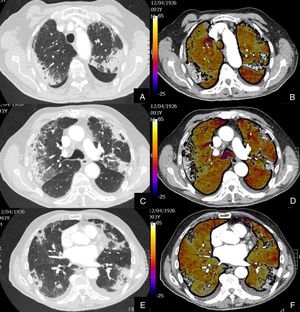

Paciente con COVID-19 que persiste con desaturación a pesar de mejoría clínica.

Imágenes axiales de la angiografía pulmonar con TC y mapa de yodo con ventana de pulmón (A, C, E) desde cayado hasta lóbulos inferiores y su correlación con las imágenes del mapa de yodo (B, D, F).

Parénquima con extensa afectación en vidrio deslustrado de predominio subpleural con consolidación de pequeño tamaño en LID, sin TEP visible, con áreas parcheadas de hipoperfusión (zonas azules) en el mapa de yodo, de predominio periférico, que coinciden con las zonas en vidrio deslustrado.